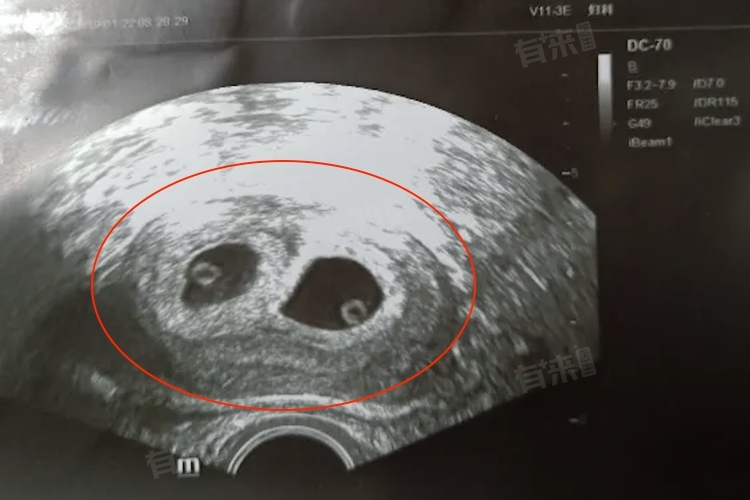

- 随着妊娠的进展,到了7-8周,超声检查对于双胞胎的检测准确性会进一步提高。在这一时期,如果确实为双胞胎,超声波图像中可以清晰地看到两个独立的妊娠囊,每个囊内都有各自的胚胎和心跳。这一发现将有力地支持双胞胎的诊断,并为后续的孕期管理提供重要依据。